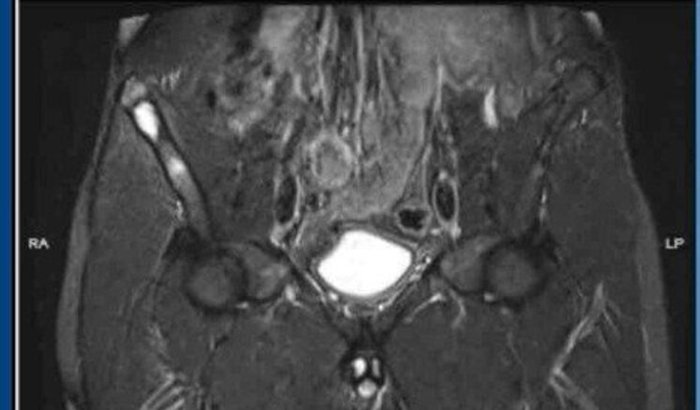

Meu marido foi diagnosticado com Osteoma Osteoide, um tumor ósseo benigno, mas que a mais de um mês vem nos dando muita dor de cabeça.

Acontece que o tumor cresceu, e desde então meu marido não consegue caminhar, trabalhar e sente dores fortes 24 horas por dia, mesmo fazendo o uso de vários medicamentos.

Vou deixar fotos dos laudos e encaminhamentos.